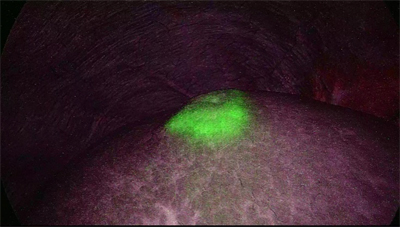

ICG(インドシアニングリーン)という特殊な検査薬を投与後、近赤外線特殊カメラを使用することによって腫瘍の位置や、リンパ流の流れ、臓器血流を確認することができ、肝、膵、大腸手術で応用しております。

ICG蛍光内視鏡による肝腫瘍の確認

膵切除の際のリンパ流の流れの検索

ICG蛍光内視鏡による大腸手術における大腸吻合部の血流確認